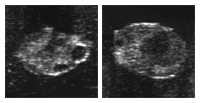

Eierstock in der Zwischenbrunst

Der Gelbkörper (Corpus luteum) produziert das Trächtigkeitshormon (Progesteron). Dieses Hormon führt über den Blutweg zu Veränderungen im Verhalten und am Genitaltrakt. Den jungen Gelbkörper nennt man auch Corpus hämorrhagicum. Dieser ist weich und von roter Farbe. Von einem reifen Gelbkörper in der Mitte des Zyklus sagt man auch, er sei in Blüte. Seine Form ist oft Champagnerzapfenförmig. Er sollte einen Anteil von mindestens 50 Prozent am gesamten Eierstock einnehmen.

Es ist möglich, dass sich während der Gelbkörperphase 1-2 Eibläschen auf dem Eierstock bilden. Man spricht von Follikelwellen und Zwischenfollikeln. Die Eibläschen gehen ohne Eisprung wieder zu Grunde. Der Gelbkörper bildet sich erst zurück, wenn von der nichtträchtigen Gebärmutter das Hormon Prostaglandin gebildet wird.